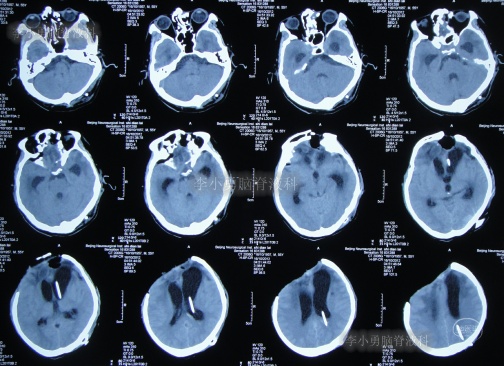

脑室腹腔分流术后7天即2012年10月23日,患者突发意识丧失、双眼上翻伴头部抖动近20分钟后自行缓解,查头颅CT(图-3)后考虑为“颅内感染”。

图-3:2012年10月23日头颅CT

脑室腹腔分流术后11天即2012年10月27日,进行了脑室腹腔分流管腹腔端外置术(图-4),术中可见清亮脑脊液流出。

图-4:2012年10月27日头颅CT

治疗期间给予腰穿脑脊液检查未见细菌,但白细胞、蛋白偏高,体温仍间断升高,最高38.6度,期间查头颅CT示脑室仍有扩张(图-5)。

图-5:2012年10月30日头颅CT